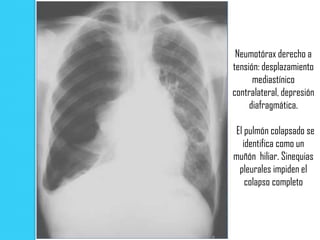

Neumotórax derecho a

tensión: desplazamiento

mediastínico

contralateral, depresión

diafragmática.

El pulmón colapsado se

identifica como un

muñón hiliar. Sinequias

pleurales impiden el

colapso completo

Signos radiológicos deNeumotórax a tensión  Colapso completo del pulmón  Depresión del diafragma homolateral  Desplazamiento del mediastino y la tráquea hacia el tórax contra lateral

Neumotórax derecho a tensión:desplazamiento mediastínico contralateral, depresión diafragmática. El pulmón colapsado se identifica como un muñón hiliar. Sinequias pleurales impiden el colapso completo